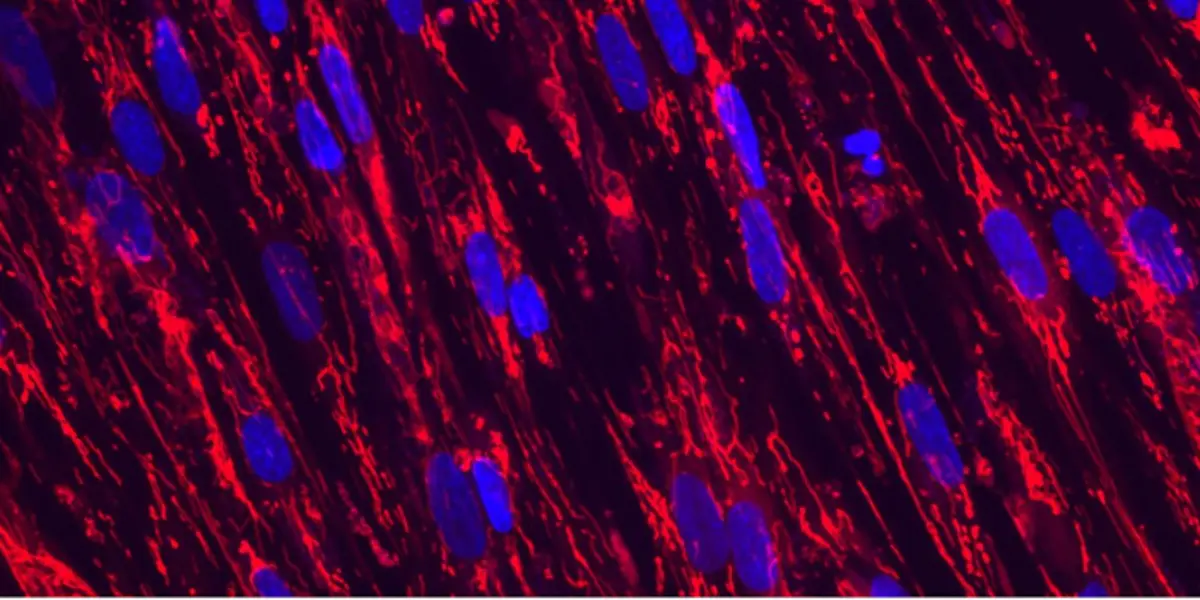

- Extracellular Matrix (ECM) alterations with age affect cellular activities and tissue structure, impacting organ function.

In addition to studying these prominent aging-relevant processes, DARe scientists are exploring the modulation of cell fate and state as a promising therapeutic strategy for the regeneration of tissue and organ function. Our strategy is based on human data and driven by our data science powered 'Regeneration Engine,’ which learns from high-resolution datasets. We utilize phenotypic screening, bioengineering, and in vitro disease models, guided by the Regeneration Engine. This approach builds on research efforts around osteoarthritis and tendinopathy and has expanded to Alzheimer's Disease and Sjögren's Disease.

Exercise can counteract diseases associated with aging and we aim to delineate the molecular and cellular mechanisms underlying the benefits of physical activity. Our approach, anchored in human data, has a particular emphasis on the hallmarks of aging, such as exercise-induced reversal of age-related mitochondrial dysfunction. Like exercise, body weight loss in the context of obesity has demonstrated health benefits across organ systems. To complement exploratory efforts on mitochondria, we are also looking at alternative approaches to increase energy expenditure in skeletal muscle for the treatment of age-related obesity.